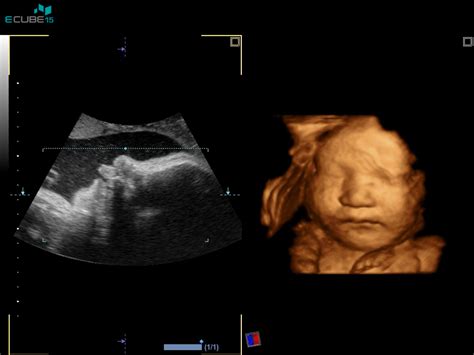

Biopsija horionskih resic je invazivna metoda prenatalne diagnostike. Pri posegu se odvzame majhen košček razvijajoče se posteljice. Postopek poteka na naslednji način:

- Priprava: Zdravnik z ultrazvokom natančno določi lego ploda in posteljice ter oceni gestacijsko starost.

- Aspiracija tkiva: S tanko iglo, ki jo vodi ultrazvok, zdravnik prodre skozi trebušno in maternično steno do horionskih resic. S pomočjo ultrazvoka se natančno orientira in odvzame majhen del tkiva. Obstajata dva pristopa:

Med celotnim postopkom zdravnik ves čas spremlja potek s pomočjo ultrazvoka, da zagotovi varnost nosečnice in ploda. Pogosto se mesto vboda predhodno infiltrira z lokalnim anestetikom, da se zmanjša bolečina. Sam postopek običajno traja le nekaj minut.

Strokovnjak pojasnjuje: ''Pri biopsiji horionskih resic se odvzame košček razvijajoče se posteljice (aspiracijska biopsija), ki ima enak genetski material kot plod. Najprej zdravnik z ultrazvokom določi lego posteljice in višino nosečnosti (z meritvijo ploda). Če presodi, da je dostopnost do posteljice ustrezna, s tanko iglo prek trebušne stene nosečnice odvzame vzorček tkiva (horionske resice). Ves postopek spremlja z ultrazvokom, da zagotovi ustrezen položaj igle. Najprej običajno infiltrira mesto vboda z lokalnim anestetikom, da je postopek manj boleč. Ko je igla na mestu posteljice, se odvzame nekaj horionskih resic (tkivo posrka prek igle in ga pošlje v laboratorij na preiskave). Sam postopek običajno traja nekaj minut.''